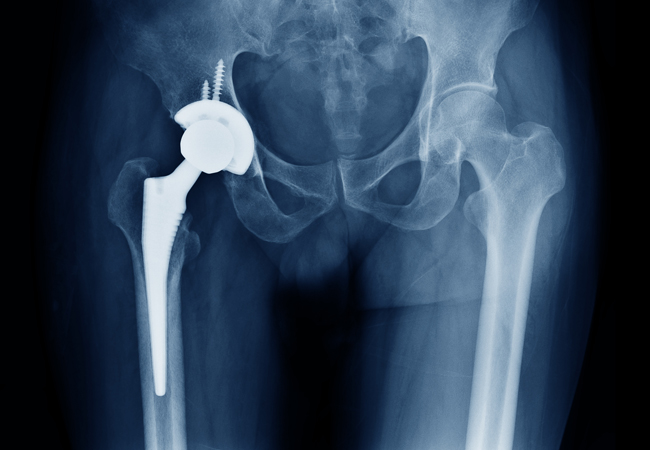

Если вы испытываете трудности при выполнении простых действий, таких как ходьба или подъем по лестнице, из-за сильной боли в коленном суставе при артрозе, то вам может подойти эндопротезирование коленного сустава. Это безопасная и эффективная процедура для избавления от боли, исправления деформации ног и восстановления нормальной повседневной жизни.(с)